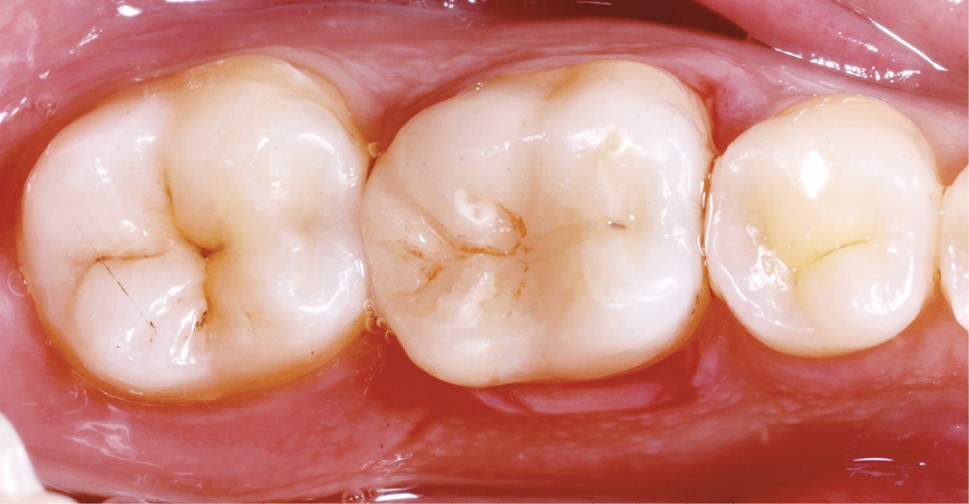

Lors de la préparation d’une cavité pour inlay/onlay, il est fréquent d’être confronté, en fin de nettoyage, à la présence d’une ou plusieurs parois résiduelles dont la résistance mécanique paraît douteuse du fait de leur localisation ou de leur épaisseur. Les parois épaisses (+ de 2 mm) peuvent généralement être conservées (cas clinique 1) et les parois fines (- de 1 mm) doivent généralement être recouvertes. Un inlay (en composite ou en céramique) est alors réalisé. Il doit avoir lui même, au final, une épaisseur globale minimale de 2 mm pour assurer sa résistance mécanique intrinsèque à la mastication. Si un recouvrement cuspidien est indiqué, la réduction occlusale doit donc se faire sur 2 mm de hauteur au minimum [1, 2].

Mais qu’en est-il des parois résiduelles d’épaisseur intermédiaire (entre 1 et 2 mm) (cas clinique 2) ?

S’il est impossible de connaître avec certitude le risque de fracture d’une cuspide, l’objectif de cet article est de donner des éléments objectifs de prise de décision de la conservation ou du recouvrement des parois d’épaisseur moyenne à la fin du nettoyage cavitaire selon la dent, l’occlusion, la forme et le volume de la cavité, la présence ou non de dentine, la vitalité ainsi que l’incidence esthétique.